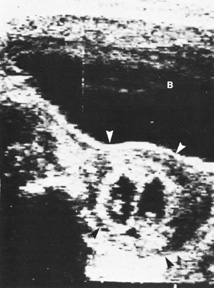

Diagnostic ultrasound is widely used in the assessment of pregnancy and the fetus. Although clinical benefits of routine ultrasonography during pregnancy have not been established, approximately 70% of pregnancies in the United States undergo ultrasound evaluation.30 Because most instruments used in diagnostic ultrasonography produce energies no greater than 10 to 20 mW cm2 (safety defined as less than 100 mW cm2), ultrasound is considered generally safe. No harmful biologic effects on instrument operators, pregnant women, fetuses, or other patients have been found. Infants exposed in utero have shown no significant differences in birth weight or length, childhood growth, cognitive function, acoustic or visual ability, or rates of neurologic deficits (see Fig. 6).

Fig. 6. A: First-trimester twin intrauterine gestations. Ultrasound examination of the pregnant uterus (arrowheads) shows the “owl eyes” characteristic of early twin pregnancies. B: Maternal urinary bladder. (Courtesy of Alfred B. Kurtz, MD)